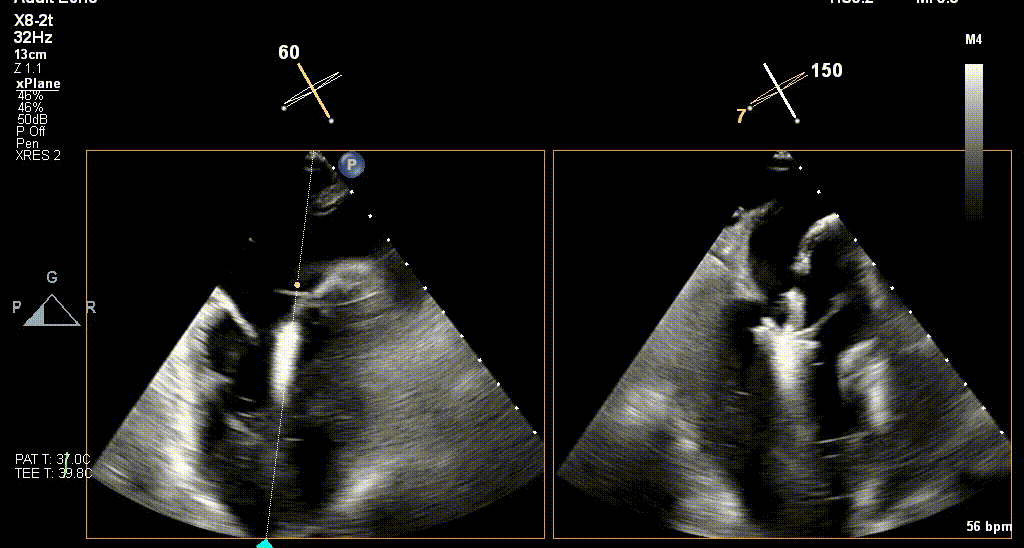

术前TEE评估

原发性MR,交界C1区脱垂,反流程度4+;二尖瓣瓣口面积3.88cm²,平均跨瓣压差2mmHg;二尖瓣前叶(A1)长度16.2mm,二尖瓣后叶长度(P1)长度9.9mm,脱垂高度6mm。